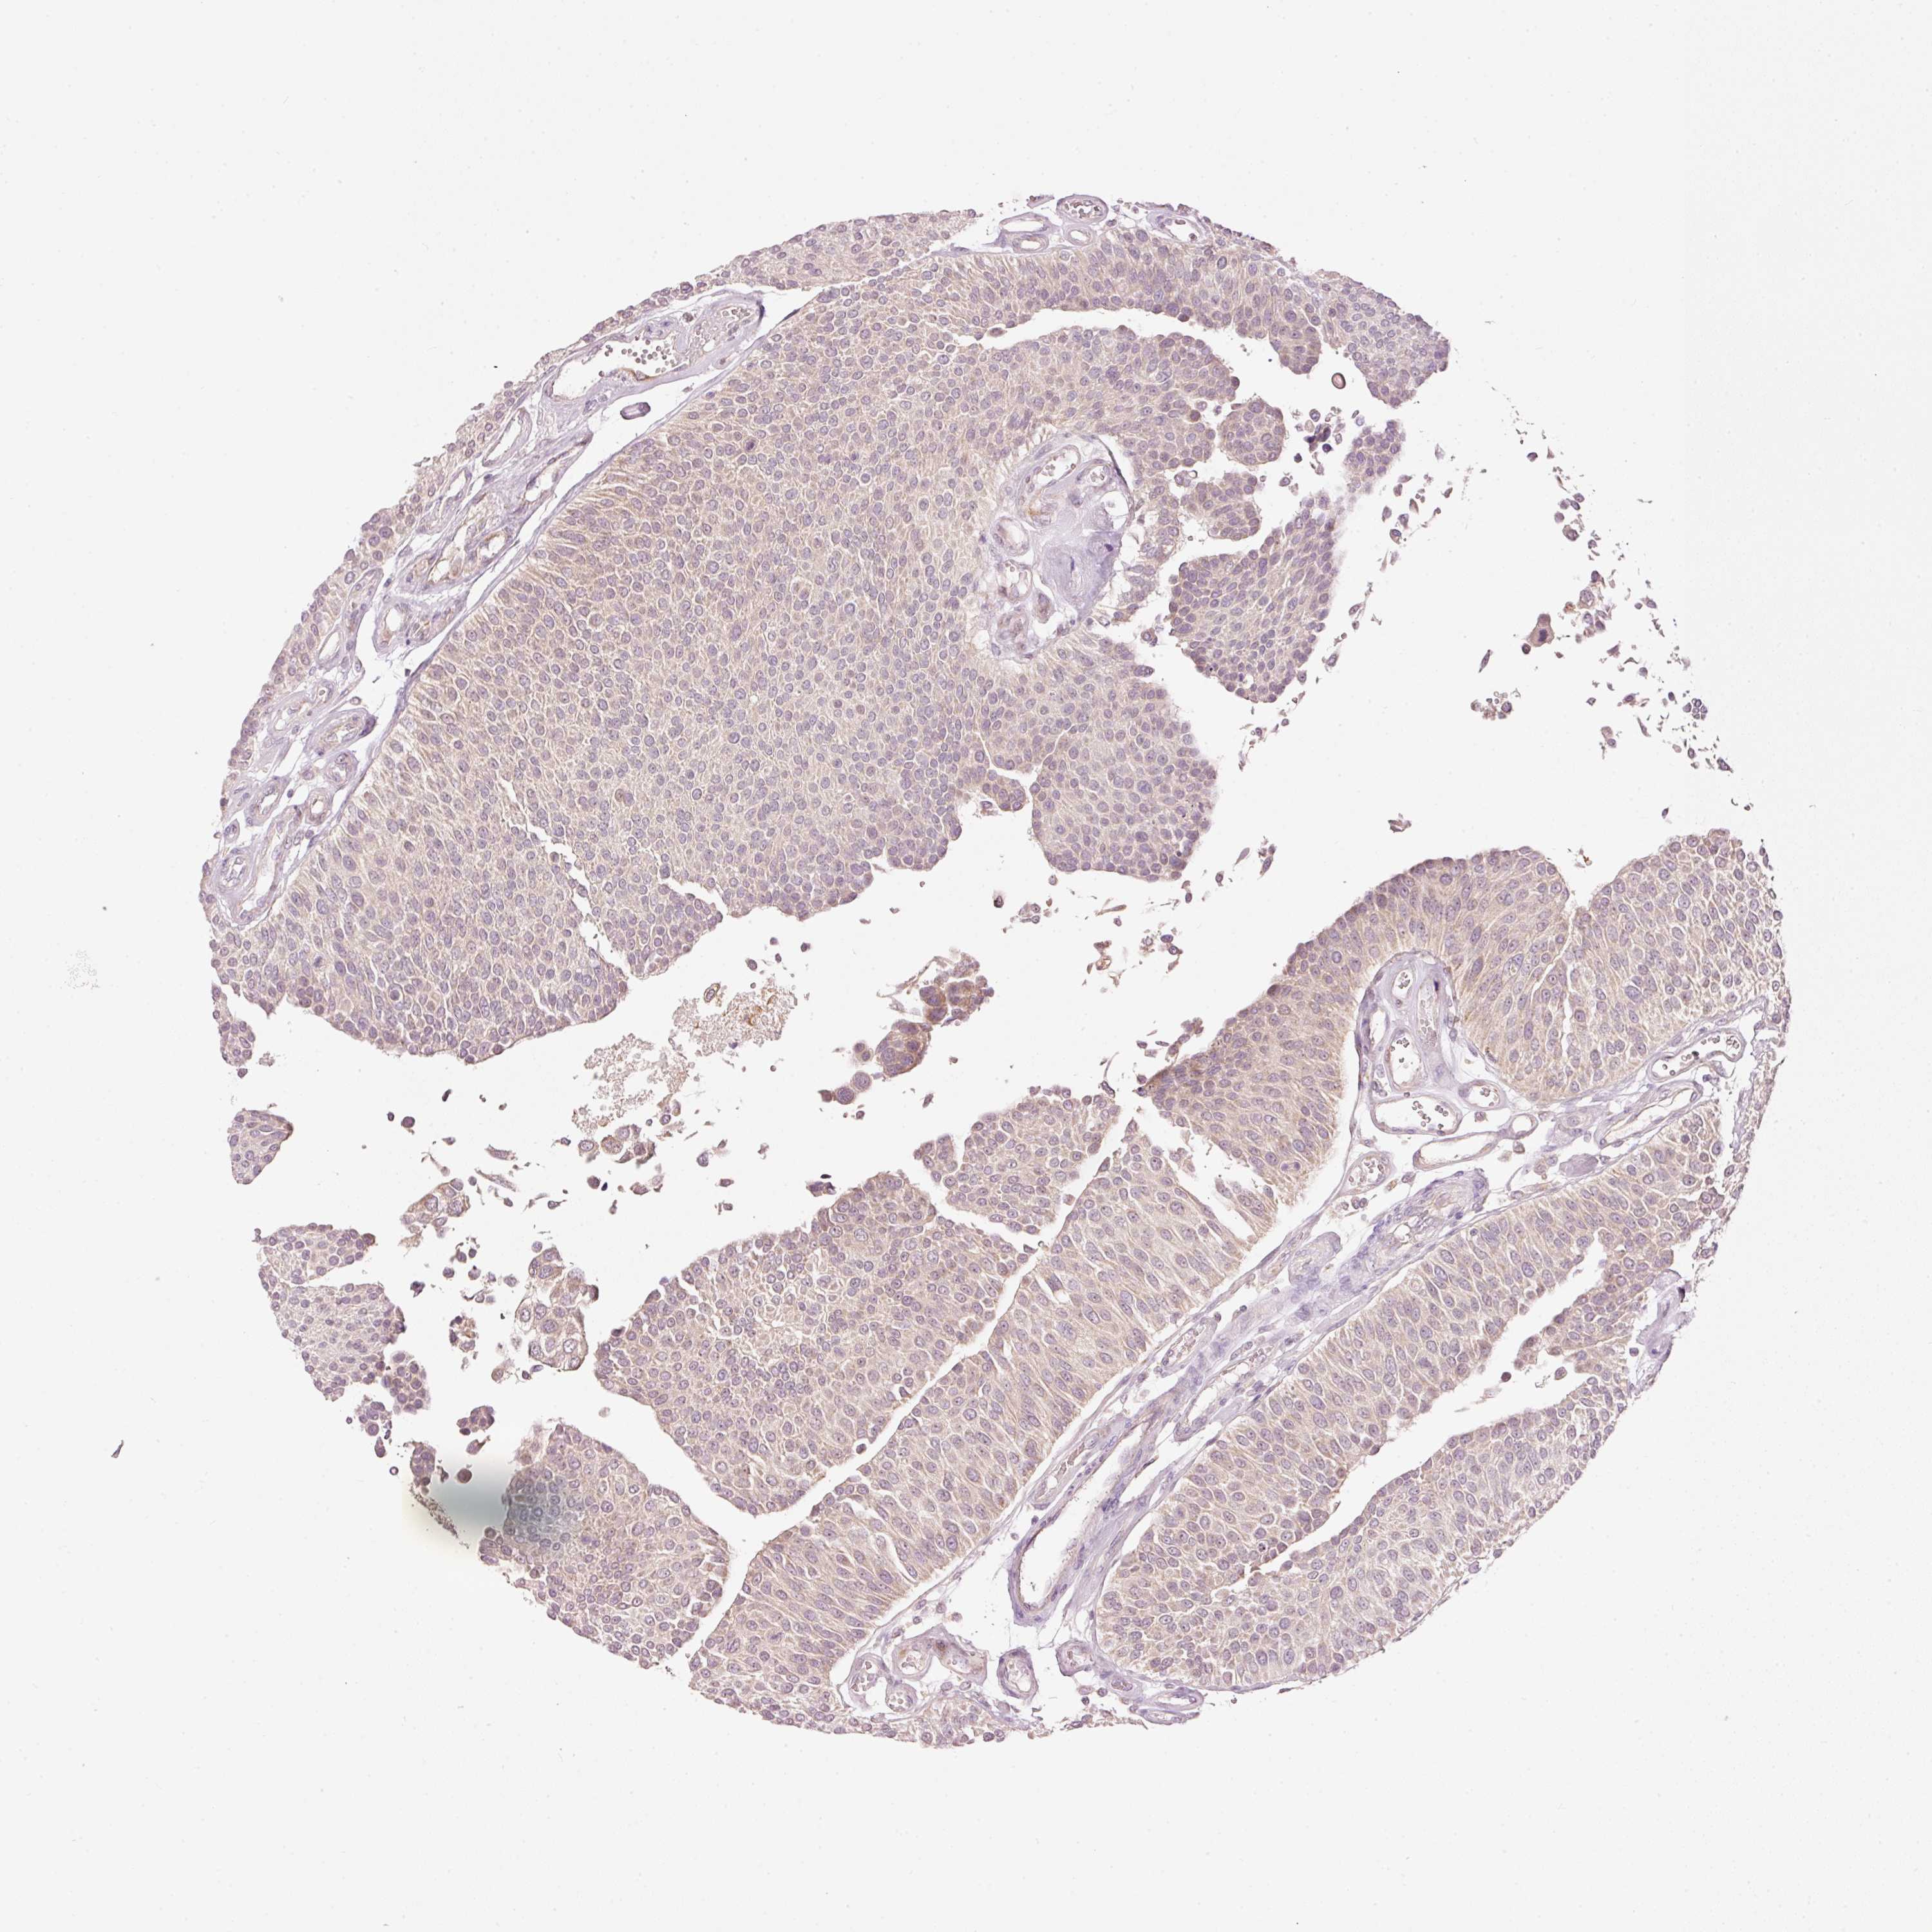

UROTHELIAL CANCER - Protein expressioni

A mouse-over function shows sample information and annotation data. Click on an image to view it in a full screen mode. Samples can be filtered based on level of antibody staining by selecting one or several of the following categories: high, medium, low and not detected. The assay and annotation is described here.

Note that samples used for immunohistochemistry by the Human Protein Atlas do not correspond to samples in the TCGA dataset.

Antibody stainingi

Antibody staining in the annotated cell types in the current human tissue is reported as not detected, low, medium, or high, based on conventional immunohistochemistry profiling in selected tissues. This score is based on the combination of the staining intensity and fraction of stained cells.

Each image is clickable and will lead to virtual microscopy that enables deeper exploration of all samples and also displays staining intensity scores, fraction scores and subcellular localization as well as patient and tissue information for each sample.

Antibody HPA053900

Staining

High

Medium

Low

Not detected

Intensity

Strong

Moderate

Weak

Negative

Quantity

>75%

75%-25%

<25%

None

Location

Nuclear

Cytoplasmic/membranous

Cytoplasmic/membranous,nuclear

Urothelial carcinoma, High grade

Urothelial carcinoma, NOS

Urothelial carcinoma, Low grade